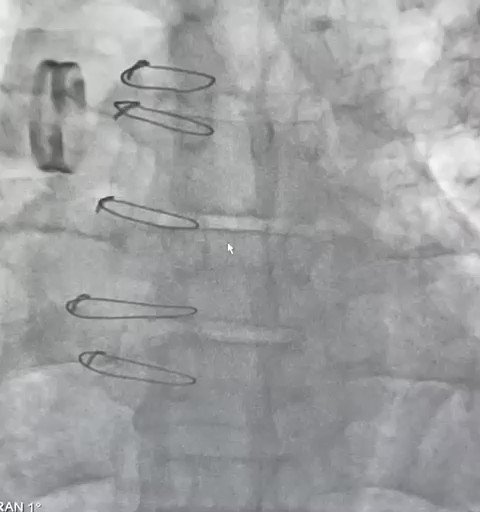

2025

OPTEM-oHCM: Optimal Targeted Polymer-based Embolization for Obstructive Hypertrophic Cardiomyopathy

JACC Case Reports

Martins Filho E, Munhoz TS, Munhoz Júnior S

Selected for "The Best of JACC" Reprint, March 2026